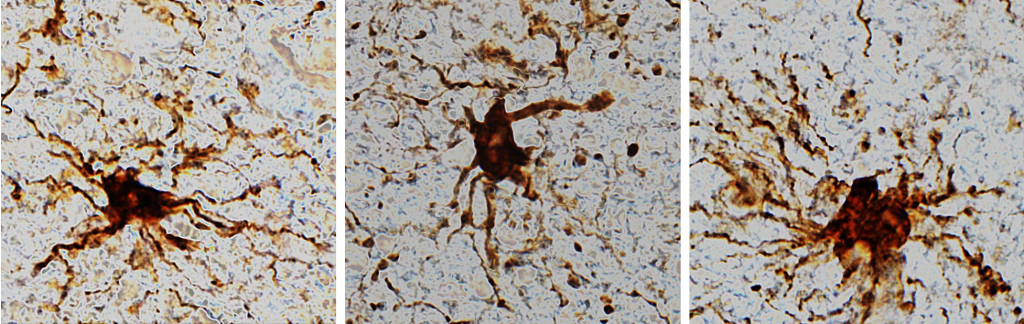

Uno de los casos más estudiados ocurre en el cerebro. Después de la muerte, ciertas células pueden aumentar su actividad durante un corto periodo. Incluso pueden cambiar de forma o tamaño antes de degradarse completamente.

Este comportamiento demuestra que las células no dejan de funcionar de inmediato. Hay una transición en la que algunos procesos continúan activos. Este descubrimiento es clave para mejorar técnicas como los trasplantes de órganos.